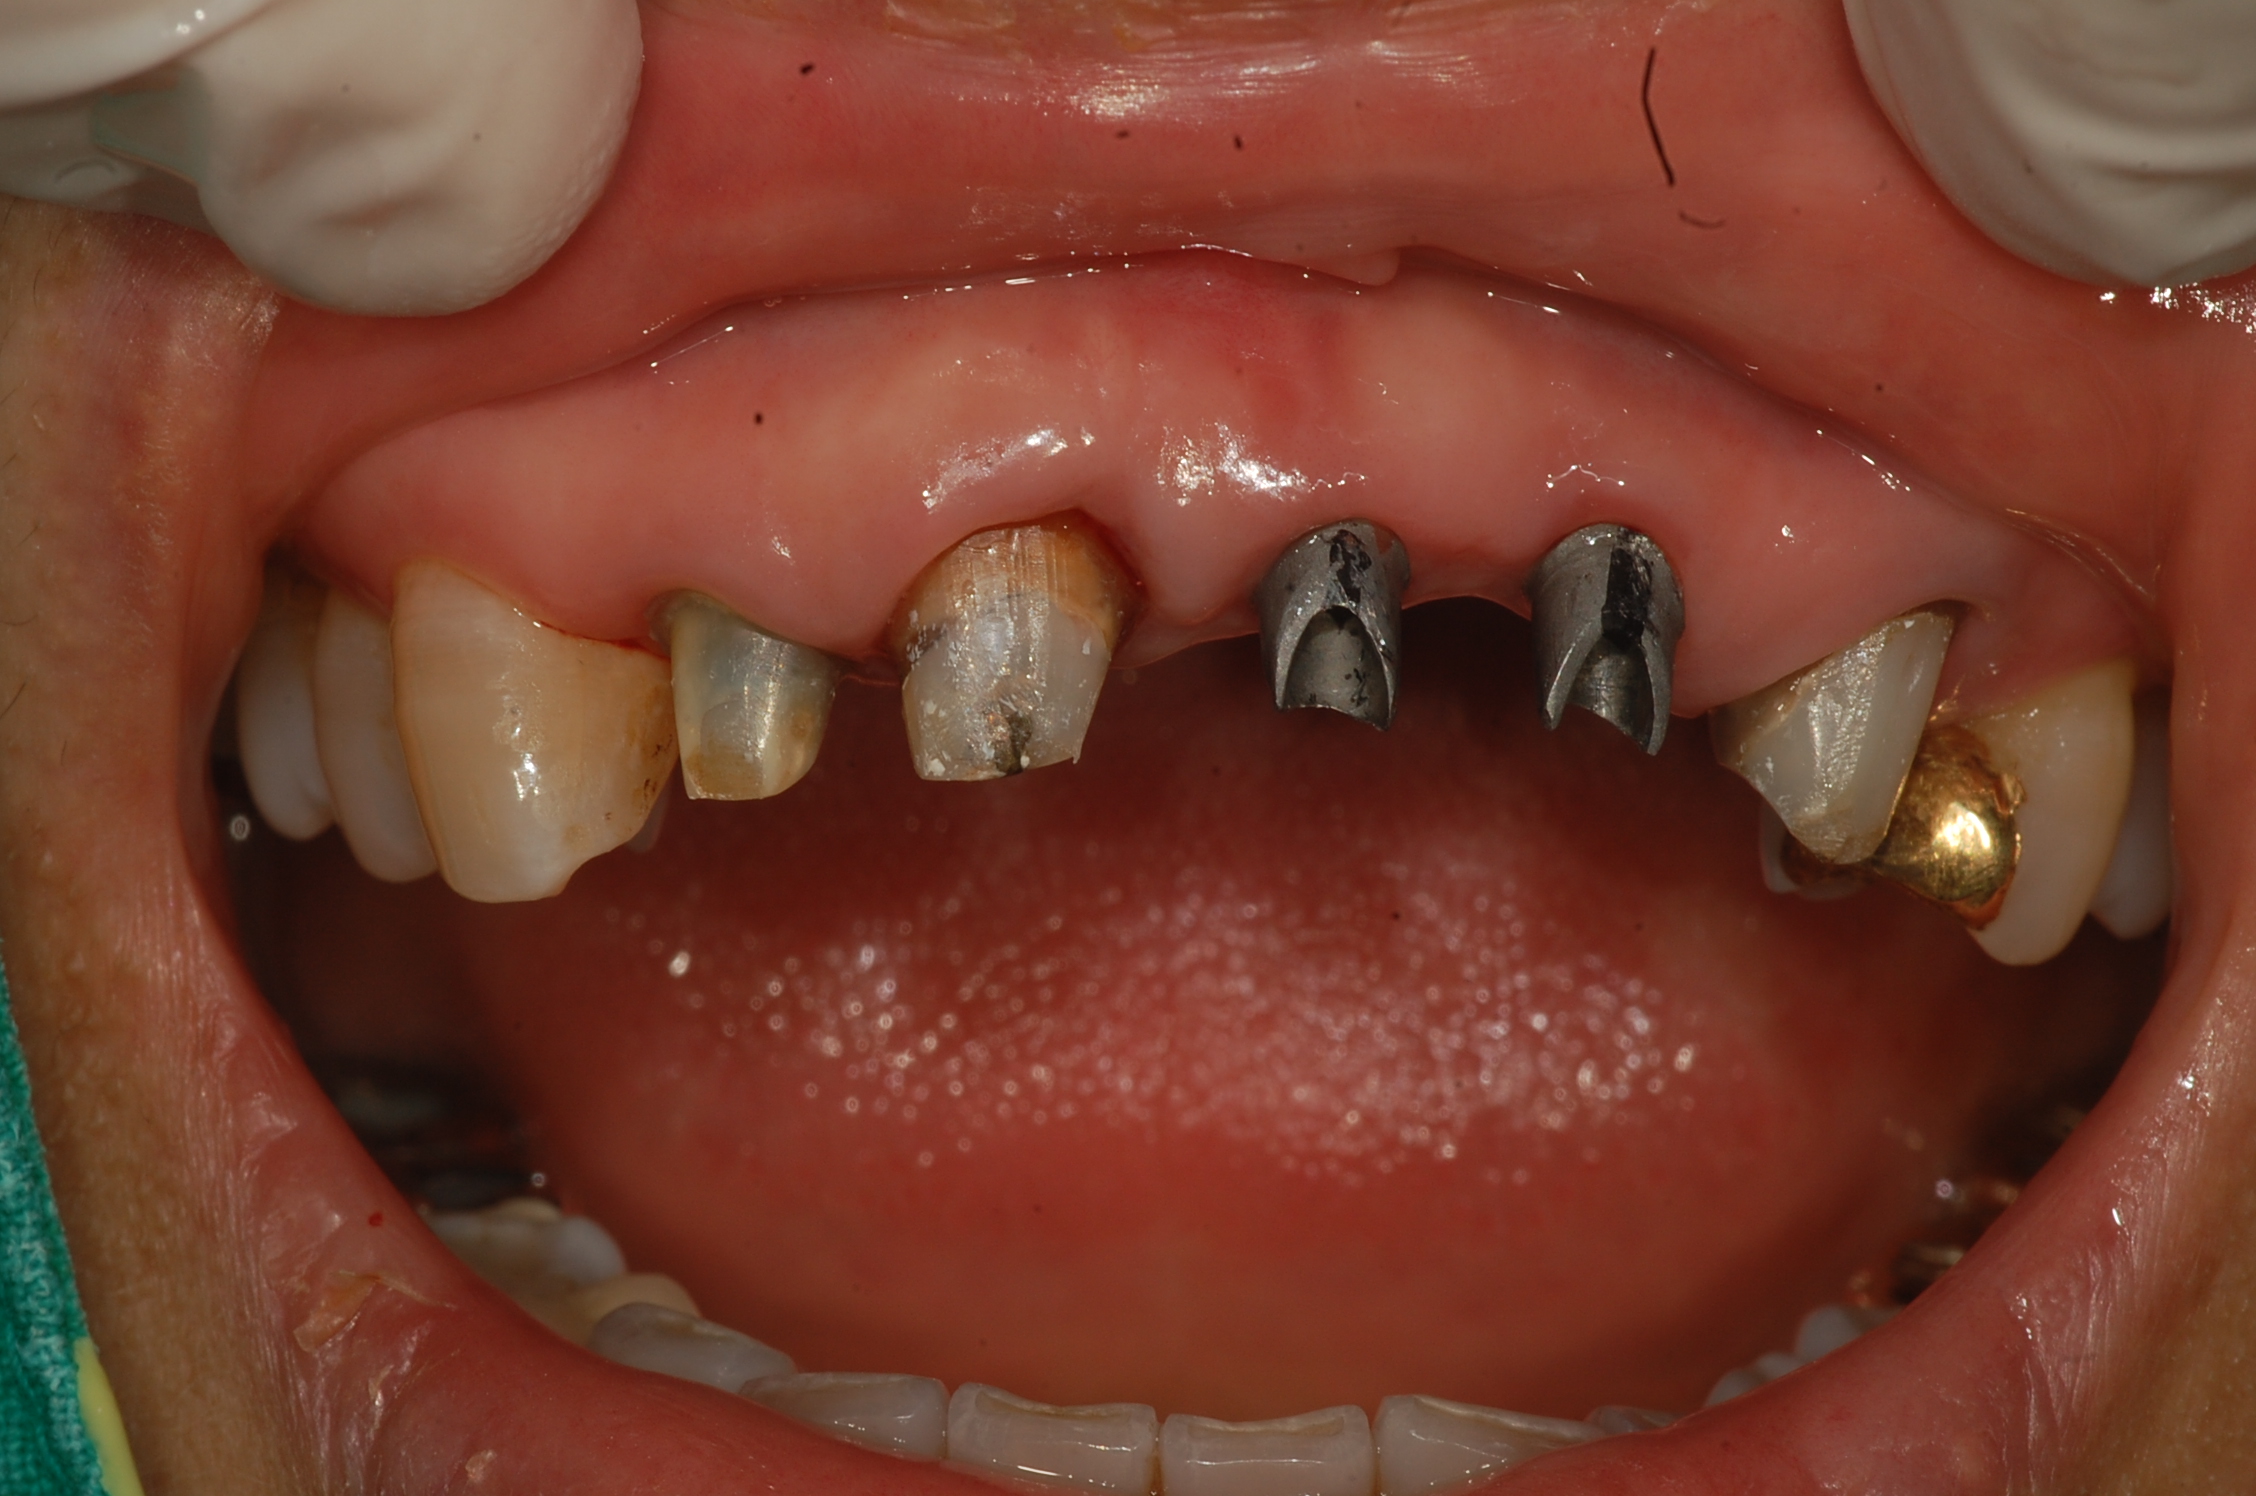

[임플란트] 제목 : 임플란트와 보철치료의 결합

오래된 보철의 파절로 일부는 임플란트로 일부는 치아 재보철로 치료하였습니다.